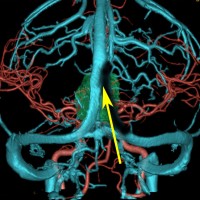

小さな松果体奇形腫です。

OTAでこの奇形腫を見ようとする場合に,テントを静脈洞交会の低い位置まで切断しなければ,直静脈洞の横から松果体部をみることはできません。また,黄色の矢印の方向に視野が入るので,まず最初に邪魔になるのは小脳上極です。上小脳層を左右ともに十分剥離すると,小脳が可動化して,その向こうに,precentral cerebellar veinが見えます。このveinをガレン大静脈への流入部から小脳前面に沿って剥離していくと,小脳上極がさらに可動化して松果体への視野が開ます。

松果体腫瘍の手術では,中脳背面を見る必要があります。特に上丘とそれに連続する後交連 posterior commissureを十分に観察するために周囲組織の剥離を行います。具体的には迂回槽と下丘の周囲のクモ膜組織を剥離します。対側中脳と迂回槽を見る時に妨げになるのが,緑の矢印で示した直静脈洞です。テントが長く切断してあって直静脈洞が大脳鎌と一緒に動かせると対側を見るのがとても簡単になります。